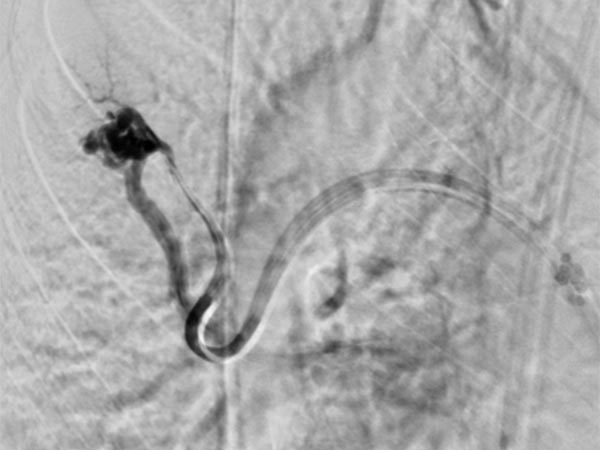

Die Abschluss-DSA über den Truncus pulmonalis zeigt keinen Zustrom mehr in die pulmonalen AVM.

Die Abschluss-DSA über den Truncus pulmonalis in der Parenchymphase bestätigt den vollständigen Verschluss der pulmonalen AVM.